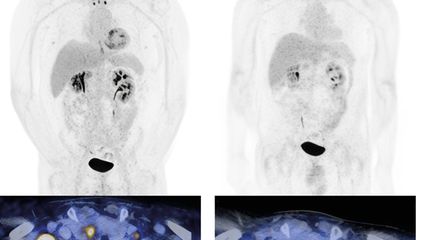

Dans une étude de phaseII, la thérapie par cellules T CAR anti-CD19 brexucabtagen autoleucel a permis d’obtenir un taux de réponse de 91% et une survie globale médiane d’environ 47 mois.15